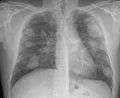

For uncomplicated silicosis, chest x-ray will confirm the presence of small (< 10 mm) nodules in the lungs, especially in the upper lung zones. Using the ILO classification system, these are of profusion 1/0 or greater and shape/size "p", "q", or "r". Lung zone involvement and profusion increases with disease progression. In advanced cases of silicosis, large opacity (> 1 cm) occurs from coalescence of small opacities, particularly in the upper lung zones. With retraction of the lung tissue, there is compensatory emphysema. Enlargement of the hilum is common with chronic and accelerated silicosis. In about 5-10% of cases, the nodes will calcify circumferentially, producing so-called "eggshell" calcification. This finding is not pathognomonic (diagnostic) of silicosis. In some cases, the pulmonary nodules may also become calcified.

A computed tomography or CT scan can also provide a mode detailed analysis of the lungs, and can reveal cavitation due to concomitant mycobacterial infection.